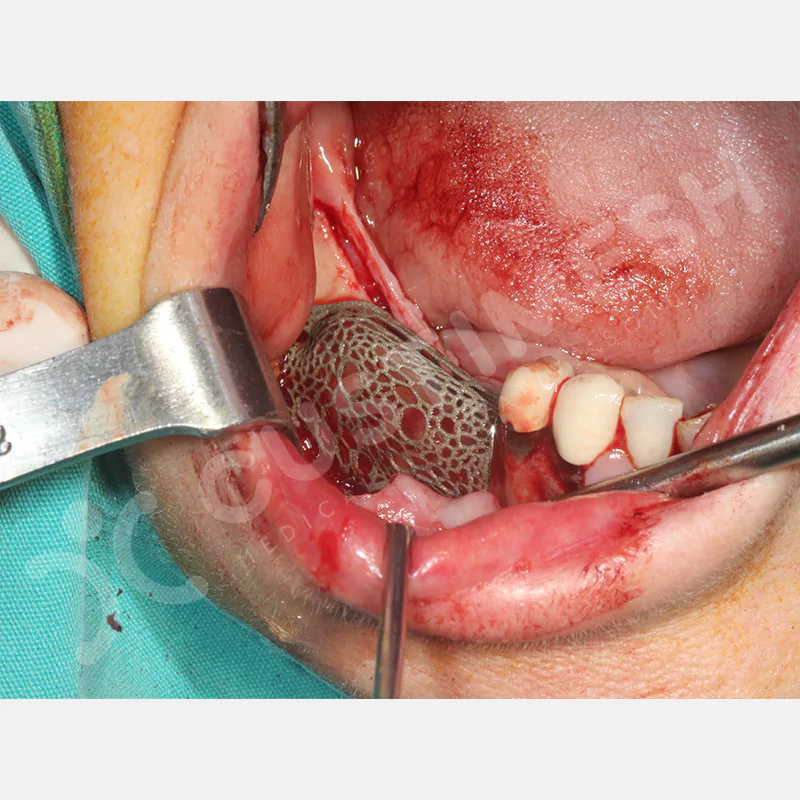

Dental implant uygulanamayan hastalarda kemik rejenerasyonunu sağlamak üzere geliştirilen kişiye özel titanyum mesh, kemik augmentasyon işlemlerinde greft materyalinin korunması ve yeni kemik oluşumunun desteklenmesi amacıyla kullanılan, hastanın kendi anatomisine tam uyumlu titanyum bir bariyer sistemidir.

Medikal sınıf titanyumdan, hastanın bilgisayarlı tomografi verileri kullanılarak CAD yazılımlarıyla tasarlanan ve 3D baskı teknolojisiyle üretilen bu yenilikçi çözüm, özellikle kompleks kemik defektlerinde standart meshlerin sağlayamadığı üstün mekanik stabilite ve mükemmel adaptasyon özellikleri sunar. Anatomik yapıya tam uyum sağlayarak greft materyalinin yerinde kalmasını garanti ederken, optimal vaskülerizasyonu destekleyerek kemik rejenerasyon sürecini hızlandırır.

- Çıkarımı Kolaylaştırmak için Özel Tasarım

- Palatinal Yada Lingualden Vidalama İhtiyacı Olmaması